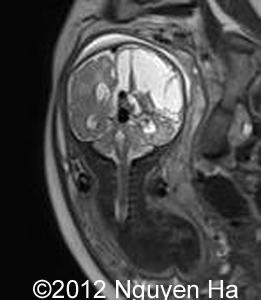

Figures 16-21:Prenatal MRI.

Figure 16-21:MRI after the first ultrasound 4 days suggesting a hematoma on the left side of the brain.